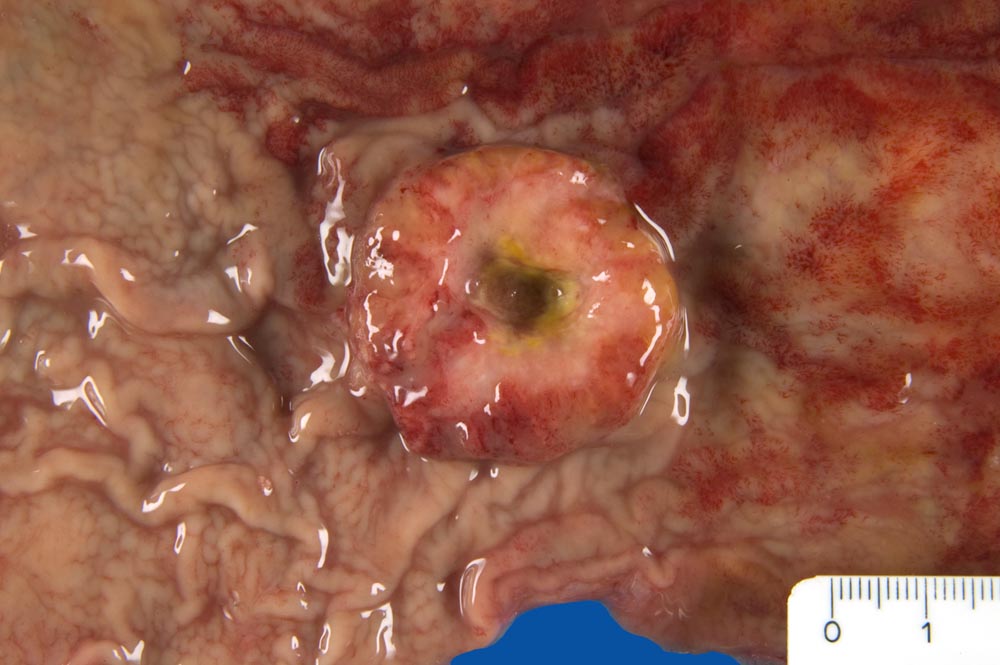

Makroskopisch können nach Borrmann (> 5050) polypoide Tumoren, ulzerierte Tumoren mit Randwall, ulzerierte Tumoren mit Invasion der Magenwand und diffus infiltrierende Tumoren (=Linitis plastica (> 3315)) unterschieden werden.

• Gewebsfragment aus gastroösophagealem Übergang.

• Das unscharf begrenzte Karzinom breitet sich diffus in der gesamten Magenwand und in der Ösophaguswand aus bis in des periösophageale und subseröse Fettgewebe.

• Ösophagus mit intaktem plattenepithelialem Schleimhautüberzug.